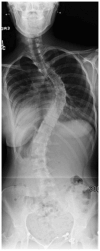

Spinal Deformity Associated with Chiari Malformation

Despite the frequency of Chiari-associated spinal deformities, this disease process remains poorly understood. Syringomyelia is often present; however, this is not necessary and scoliosis has been described in the absence of a syrinx. Decompression of the hindbrain is often recommended. In young patients (<10 years old) and/or those with small coronal Cobb measurements (<40°), decompression of the hindbrain may lead to resolution of the spinal deformity. Spinal fusion is reserved for those curves that progress to deformities greater than 50°. Further research is needed to understand the underlying pathophysiology to improve prognostication and treatment of this patient population.